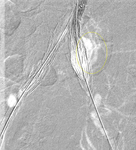

Endofuga tipo I en anastomosis distal de la ilíaca izquierda (fuga marcada con un círculo)

University of Michigan, específicamente los casos del Dr. Upchurch que reflejan los Departamentos de Cirugía Vascular y Radiología